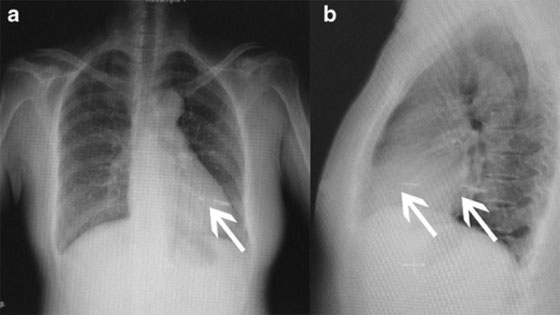

تعرضت إمرأة صينية تبلغ من العمر 48 عاما لسكتة دماغية نقلت على إثرها إلى المستشفى، وبعد القيام بالفحوصات تبين للأطباء، وجود إبرة في عضلة قلب السيدة كانت السبب في إصابتها. وأظهرت الفحوصات أن الإبرة كانت قد اخترقت صدر السيدة الصينية قبل عدة أشهر، وبقيت عالقة في عضلة قلبها قبل أن تفقد وعيها لدقائق في أحد الأيام، ما جعلها تقرر التوجه إلى المستشفى للاطمئنان على حالتها الصحية.

وبقيت الإبرة عالقة في عضلة قلب السيدة الصينية لشهور ورغم هذا، لم يذكر التقرير أسباب اختراق الإبرة صدر المرأة. وأضاف التقرير أن الإبرة، بعد اختراقها صدر السيدة الصينية، تجمع حولها الدم مشكلا كتلة دموية متكلسة. وهذه الكتلة هي التي أدت بعد انتقالها إلى الدماغ إلى فقدانها الوعي. وكان يفترض أن تشعر المريضة التي توغل في قلبها جسم غريب بأعراض كألم في الصدر، وصعوبة في التنفس، وعدم انتظام في دقات القلب، والتهاب في القلب، إلا أن أيا من هذه الأعراض لم تظهر على السيدة الصينية. وقد توجهت المرأة إلى المستشفى بعد أن فقدت وعيها لعدة دقائق، كما سبق لها أن تعرضت لنوبة دماغية أدت إلى تعثر نطقها.

وقال الطبيب المعالج إن الجسم الغريب كان عبارة عن إبرة طولها طول أصبع، وأضاف أن ما جعل الأعراض لا تظهر على المريضة هو كون الثقب الذي أحدثته الإبرة في عضلة القلب أغلقه الدم المتكلس. وقال الطبيب إن المريضة كانت بحاجة لإجراء عملية جراحية لإزالة الإبرة من صدرها، ولحسن الحظ لم تظهر عليها أي مضاعفات عصبية.